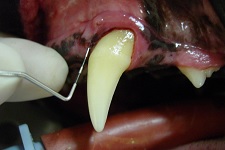

While assessing a dog’s mouth before you start to scale and polish it, you are able to perform the following with your periodontal probe:

Periodontal Pocket May 2009-01 Periodontal Pocket May 2009-02

The periodontal probe passes under the gingiva and disappears completely.